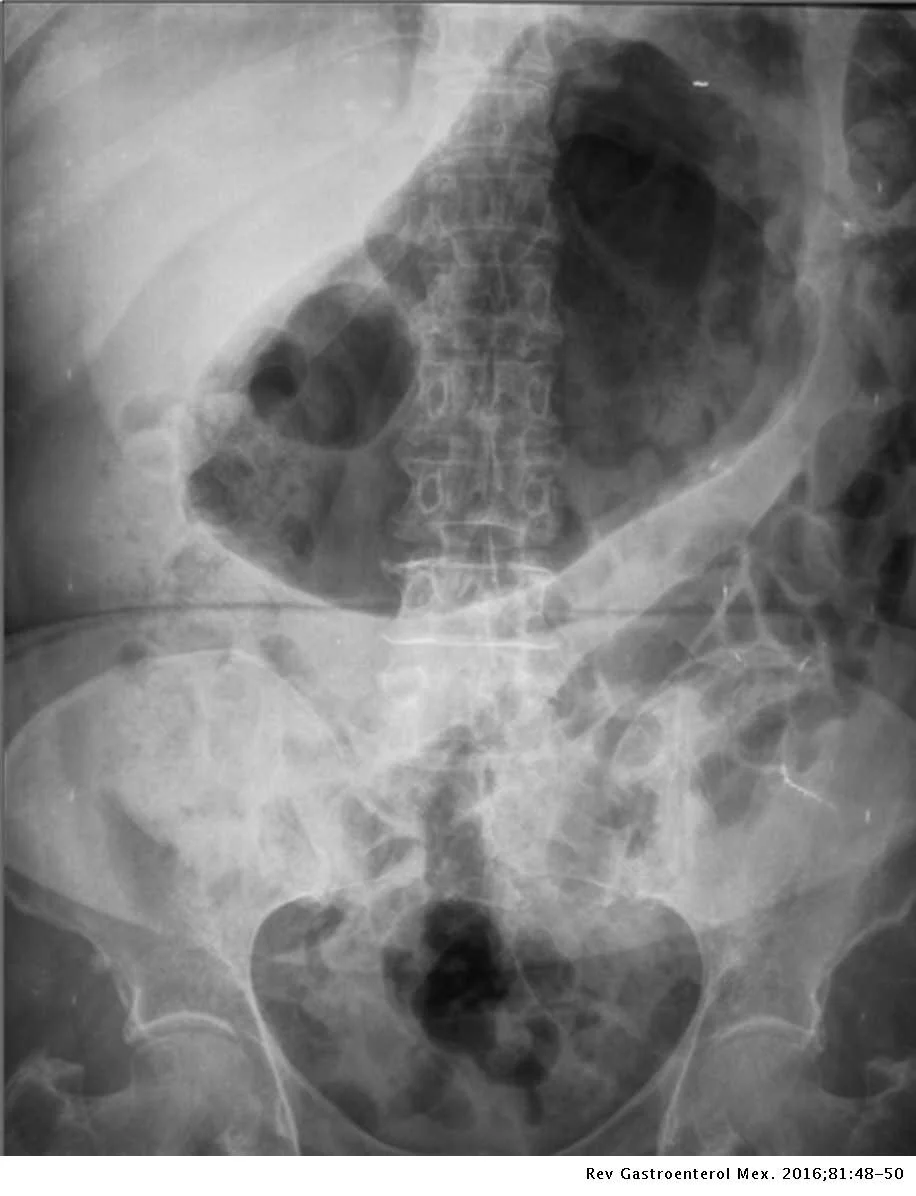

What is the pathological abnormality in this abdominal x-ray?

gr3.jpeg

Answer:

Gastric dilation (enlargement and distension of gastric chamber with air)

Question 4

What are possible causes of the above presentation?

1. Gastric outlet obstruction - pyloric ulcer/carcinoma causing mechanical obstruction. 2. Atonic Dilation - post-operative complication, diabetic coma, trauma, pancreatitis, hypokalaemia causing aperistalsis

Question 5

How would you treat this presentation?

Nasogastric aspiration